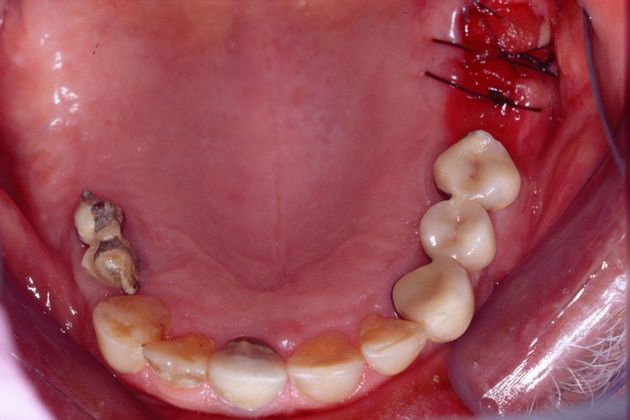

Procedures; orthodontics, gum repositioning, implant revision and new implant placement, root canal, full mouth reconstruction with crowns and implant retained crowns, bite guard therapy.

This patient wanted his smile to look better. He had a severe life long grinding habit that decimated his teeth, causing fractures, tooth loss and collapse of his bite. He wanted the best possible outcome. His was a complicated treatment that required the coordination of treatment of several specialists, much patience on his part, and resulted in an impressive result.